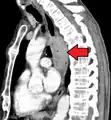

Contrast CT scan showing an esophageal tumor (axial view)

Contrast CT scan showing an esophageal tumor (coronal view)